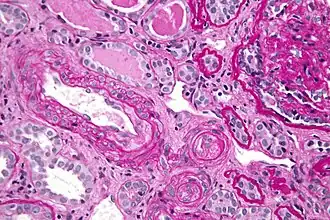

![]() Микрофотография тромботической микроангиопатии. | |